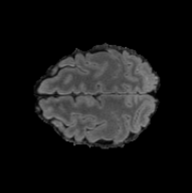

To see when and how X-Diffusion fails, we conducted an experiment on healthy brains (no tumour) using IXI dataset, by running an X-diffusion trained on BRATS brain tumor dataset. Our X-Diffusion achieved a PSNR of 35.86 dB on the IXI dataset despite being trained on the BRATS dataset. We then ran the tumour segmenter on the set of 582 healthy scans and corresponding generated MRIs. The segmenter predicted tumours in 9.9% of the real healthy brains and in 11.3% of the generated brain MRIs. Some of these tumor hallucination examples fron X-Diffusion generation are shown in Figure 10.